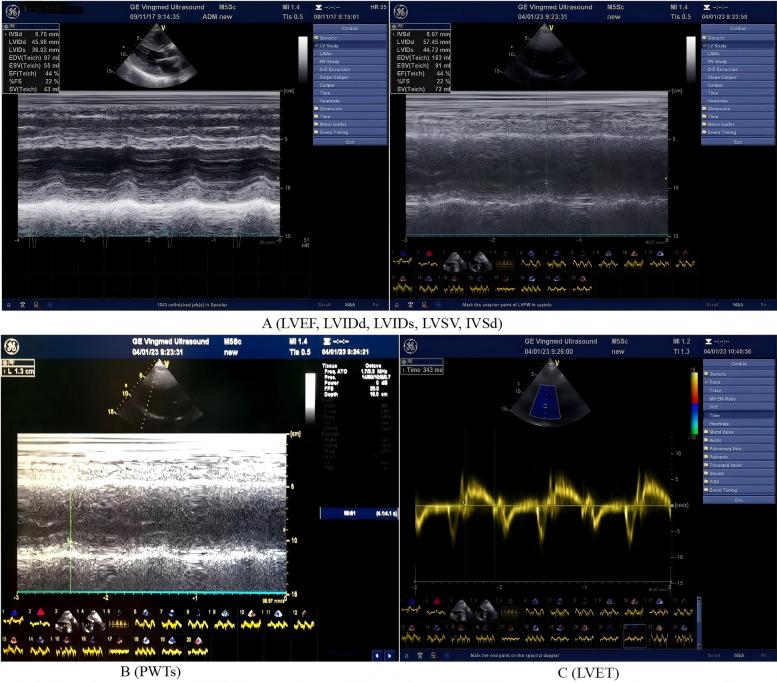

METHODS

A retrospective analysis was conducted on data from 244 inpatients admitted to our center, who were diagnosed with AMI complicated by HF. Among these patients, 210 completed a 1-year follow-up. According to the use of angiotensin-converting enzyme inhibitors (ACEI)/angiotensin receptor blockers (ARB)/ARNI, the 210 patients were divided into the ARNI group (107 cases, 51.0%) and the non-ARNI (ACEI/ARB) group (103 cases, 49.0%). The main outcome measures were the changes in myocardial energy expenditure (MEE) and prognostic indicators after 1-year follow-up.